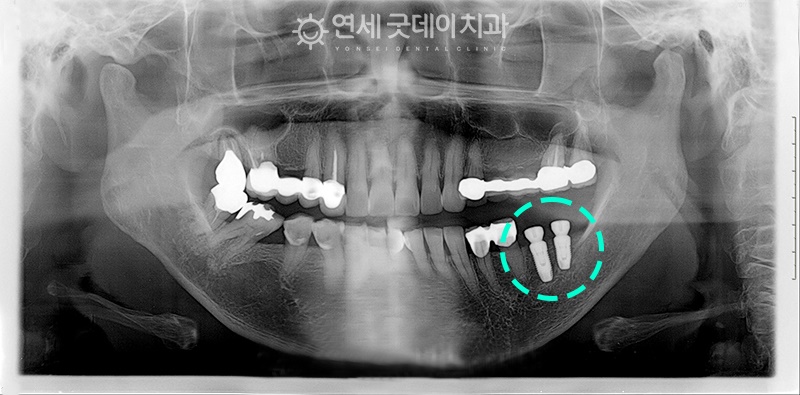

치료 전

(2006년 식립/18년 전)

18년 전 파노라마 사진입니다.

이미 타병원에서 보철치료를 많이 하셨지만

관리가 제대로 이루어지지 않아

흔들리고 염증으로 인해 치조골 소실이

진행중인 상태였습니다.

환자분은 기존에 부분틀니를 착용하셨기 때문에

틀니고리를 먼저 제거한 후

왼쪽 아래어금니 부위에

덴티움 임플란트 2개 식립해드렸습니다.

틀니고리를 제거하면서

implant와 골이식을 동시에 하는

‘발치 즉시 임플란트’를 진행해드렸습니다.